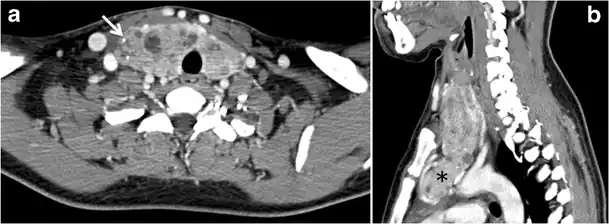

Fig. 13. A 27-year-old female patient known to have goiter. a, b Axial and sagittal enhanced CT scan images of the neck demonstrate a heterogeneously enhancing, enlarged thyroid gland with scattered calcifications (white arrow), cystic changes, and substantial retro-sternal extension (black asterisks). No lymphadenopathy or substantial airway narrowing.[1]